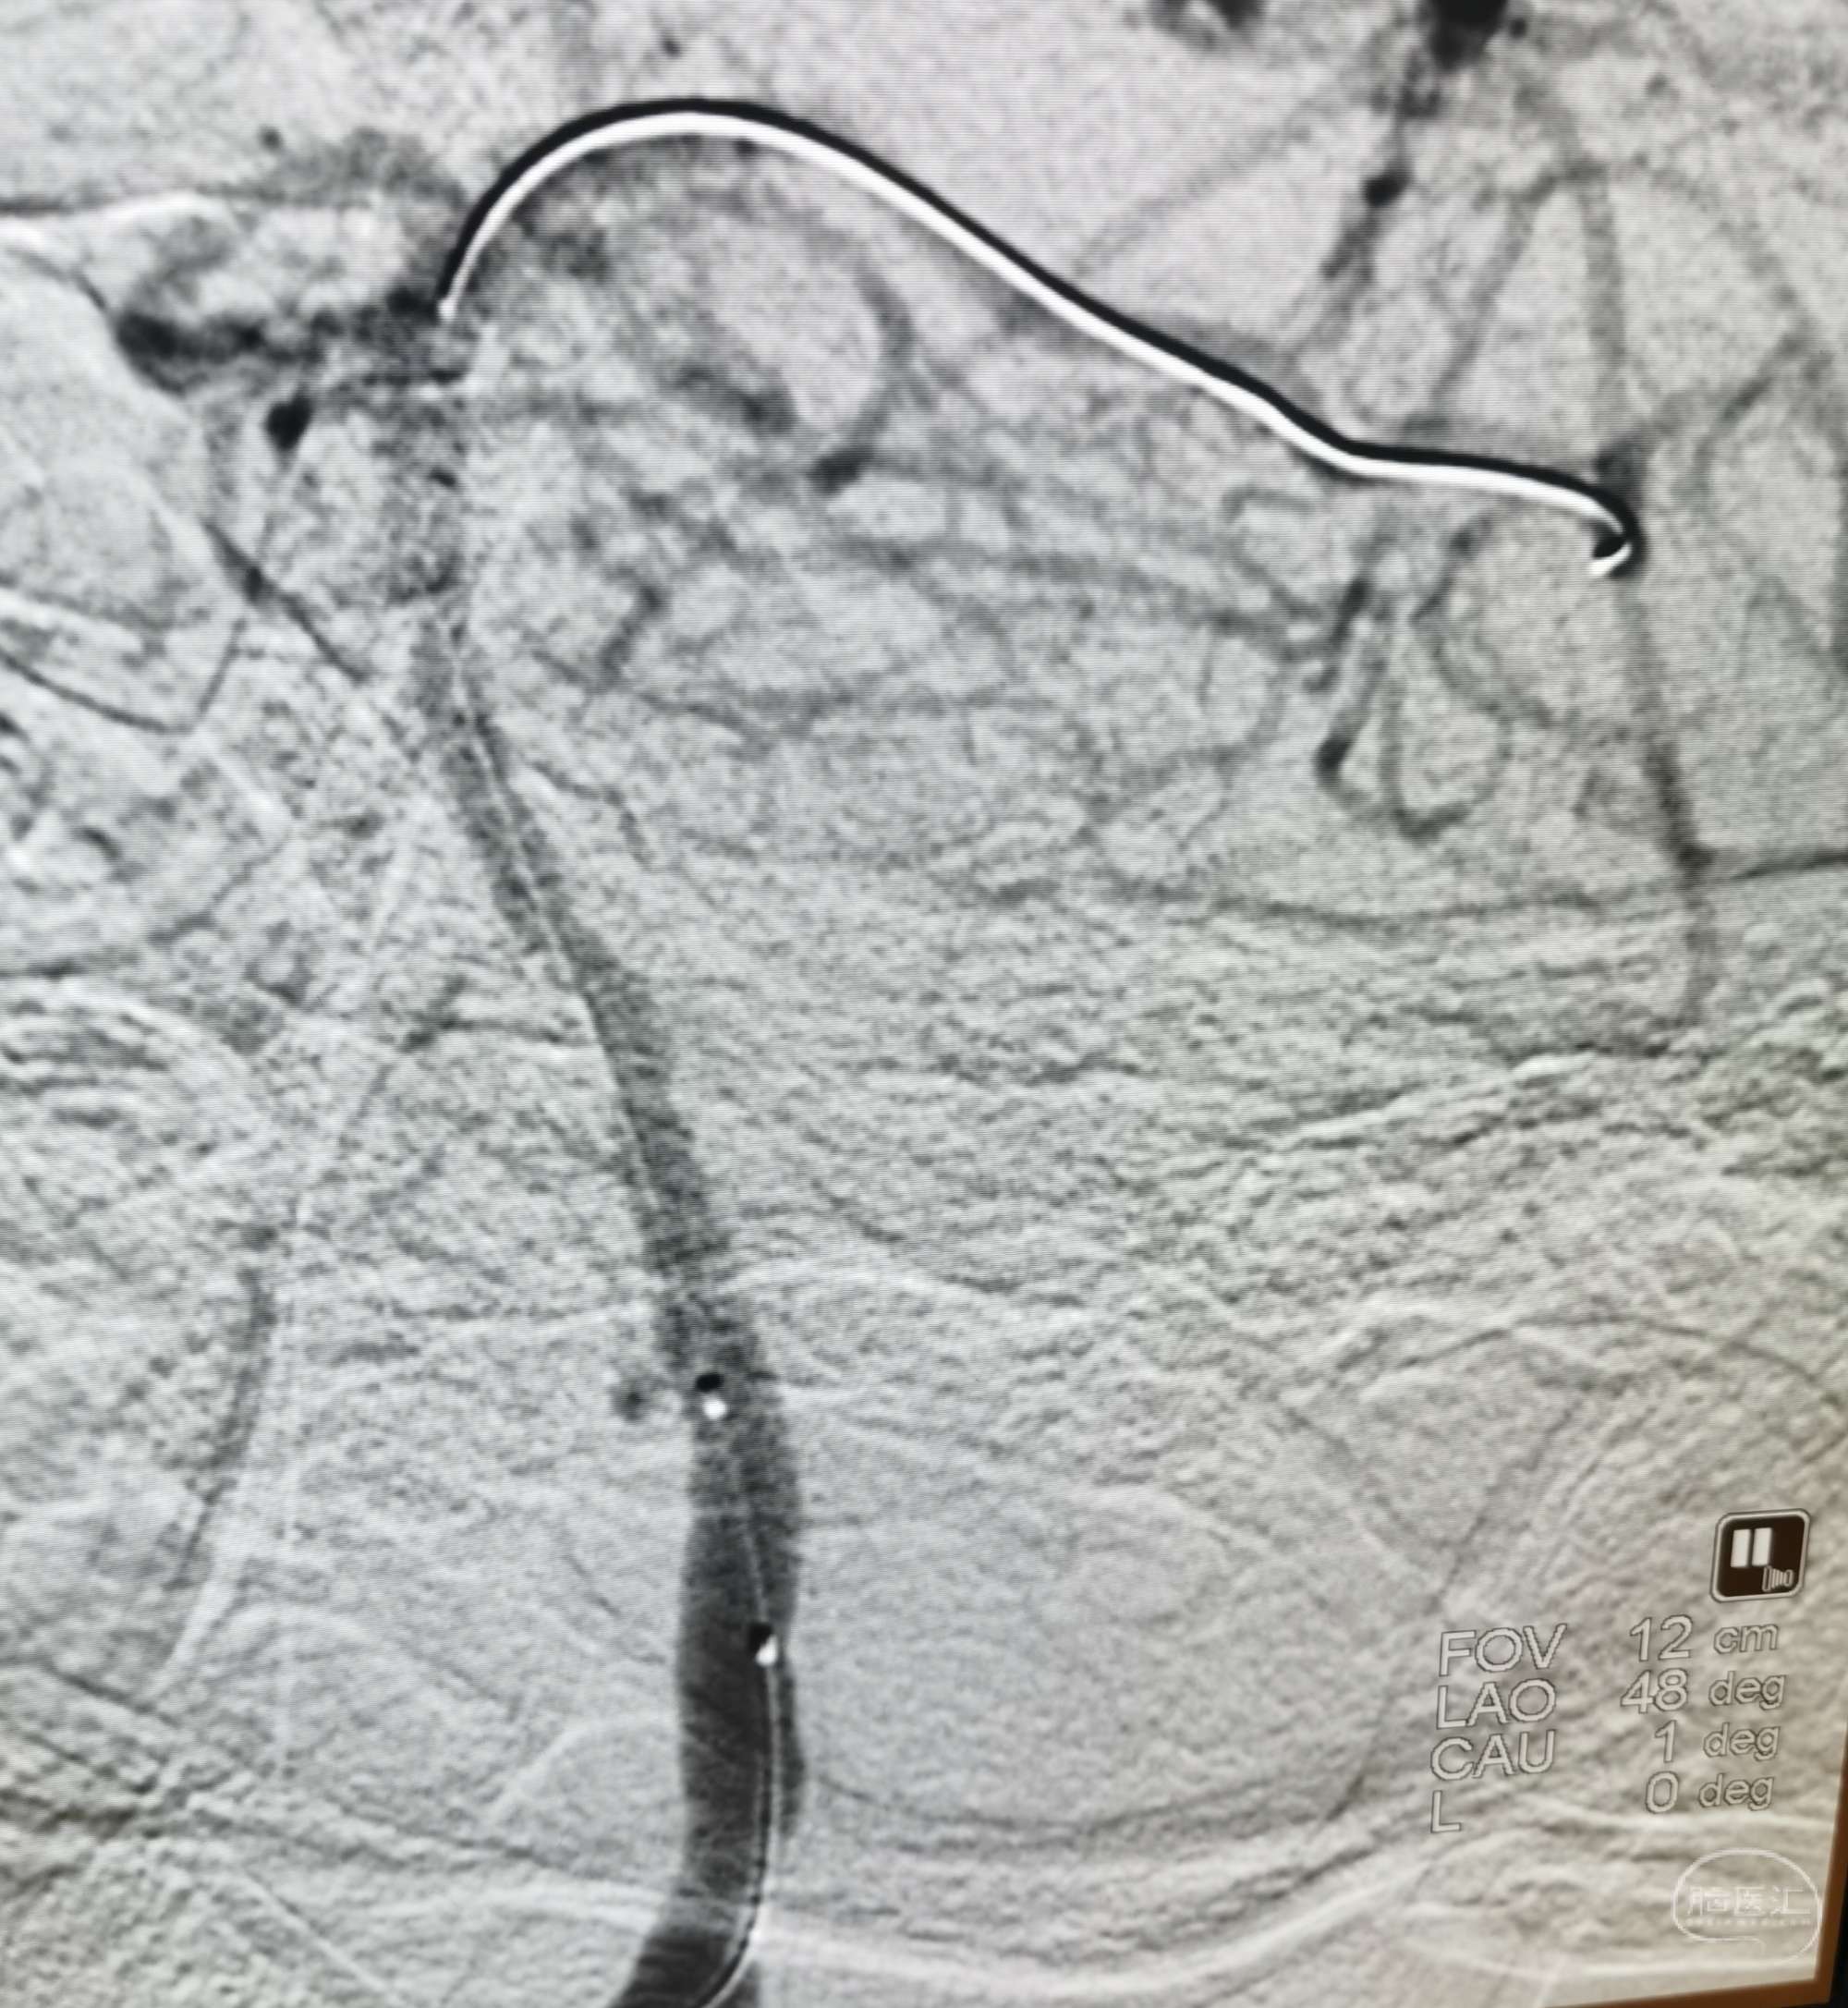

病例3 中年男性,因头晕、行走不稳半月入院。诊断:基底动脉重度狭窄。

DSA示:基底动脉中下段重度狭窄。

3D重建。

先用Gateway2.5×13mm预扩。

置入NeuformEZ 3.5×20mm支架。

血管狭窄明显改善。